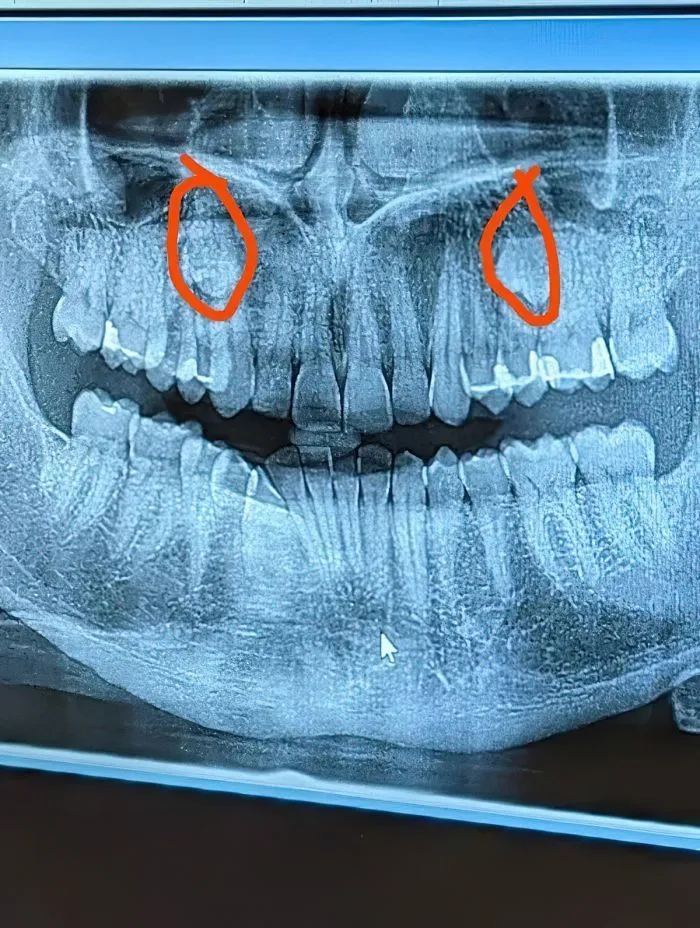

15. Человек пошёл к зубному с жалобой на боль и узнал, что у него есть лишние зубы

— Сверхкомплектные зубы. Надо было вылечить, когда ты был моложе, у тебя было бы больше возможностей. Это может передаваться по наследству.